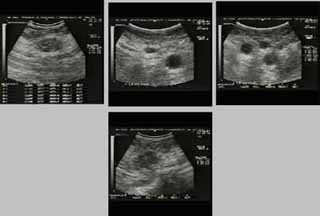

Η κλινικο-υπερηχογραφική διερεύνηση του μαστού είναι μία ακίνδυνη και πολύ αποτελεσματική μέθοδος εντόπισης εστιακών ευρημάτων.

Οι απεικονίσεις των περιστατικών που επιδεικνύονται παρακάτω, έγιναν με κυρτές κεφαλές 3,5 και 5 ΜΗΖ, προκειμένου να φανεί, ότι και με τον εξοπλισμό αυτό, που σιγά-σιγά διαθέτουν όλο και περισσότερα ιατρεία, είμαστε σε θέση να έχουμε ικανοποιητικά αποτελέσματα.

Oι τελευταίες 4 απεικονίσεις έγιναν με ειδικό για μαστό ηχοβολέα linear, εναλλασσομένης συχνότητος 7,5-10ΜΗΖ.